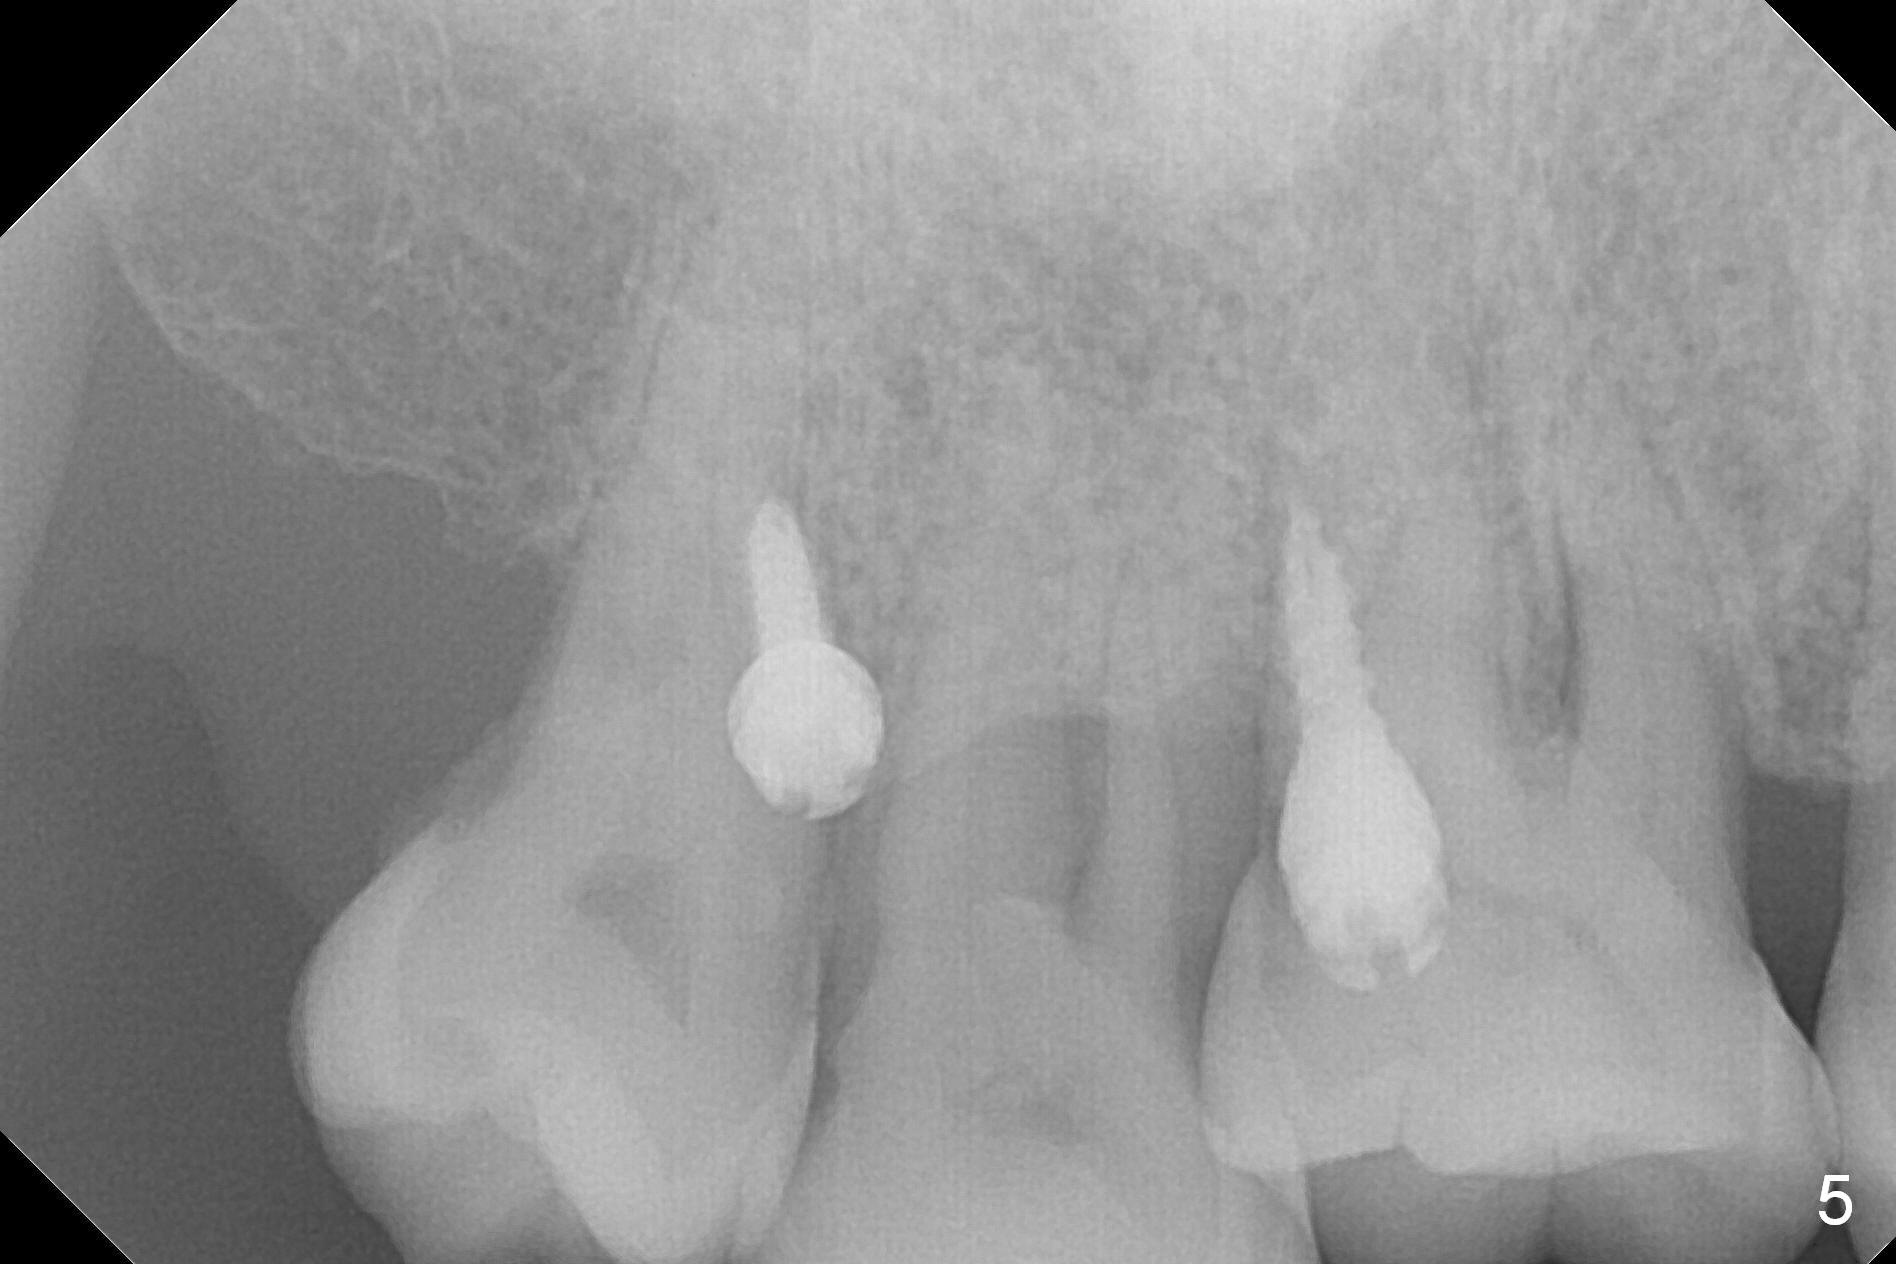

Two days post #31 implant placement, the patient returns for orthodontic intrusion of the tooth #2 with mini-implants (Fig.1). The palatal cusps have been trimmed (Fig.2 ^), since they almost contact a healing abutment at #31(*, Fig.3). Two mini-implants are to be placed mesiobuccal and distopalatal to the affected tooth. After minimal injection of Lidocaine, a 1.6x6 mm Tomas implant is placed in full length mesially (Fig.4), while the other (1.6x8 mm) half way (Fig.4). Following change in implant site mesially (Fig.6 >), the implant is half inserted (Fig.5). It appears that the tip of the distal implant is toward the tooth #1 (Fig.5). After withdrawing the implant partially, it is re-directed to apparently ideal trajectory (Fig.7). Ideally the mesial implant (Fig.8) should have been placed partially initially (Fig.4,5,7) so that the trajectory could have been able to be changed.

The buccal implant becomes loose in 2-3 months. When the wound heals (Fig.9 <), a 1.6x`10 mm implant is placed with the help of PAs for trajectory (Fig.10,11) and in the nonkeratinized gingiva (higher, the crestal bone may have been traumatized by previous implant placement, Fig.12). Two months later, the tooth #2 is partially intruded (Fig.13). A provisional (Fig.14 P) is fabricated in the osteointegrated implant at #31 with supraocclusion so that the remaining dentition has no occlusal contact (*). The periodontally compromised tooth #2 becomes in buccoversion in 2 months. The provisional is removed, while a lingual button is placed in the buccal surface of the tooth #2 (Fig.15). With power chain attached to the lingual mini-implant, the tooth #2 is lingualized in 2 months. The provisional and the implants are reused for final intrusion (Fig.16). The treatment is nearly 11 months. The buccal implant, although placed in the movable mucosa, remains stable and healthy (Fig.17). The tooth #1, as a guiding plane (to prevent #2 from distalization during intrusion), is not extracted after intrusion is completed.